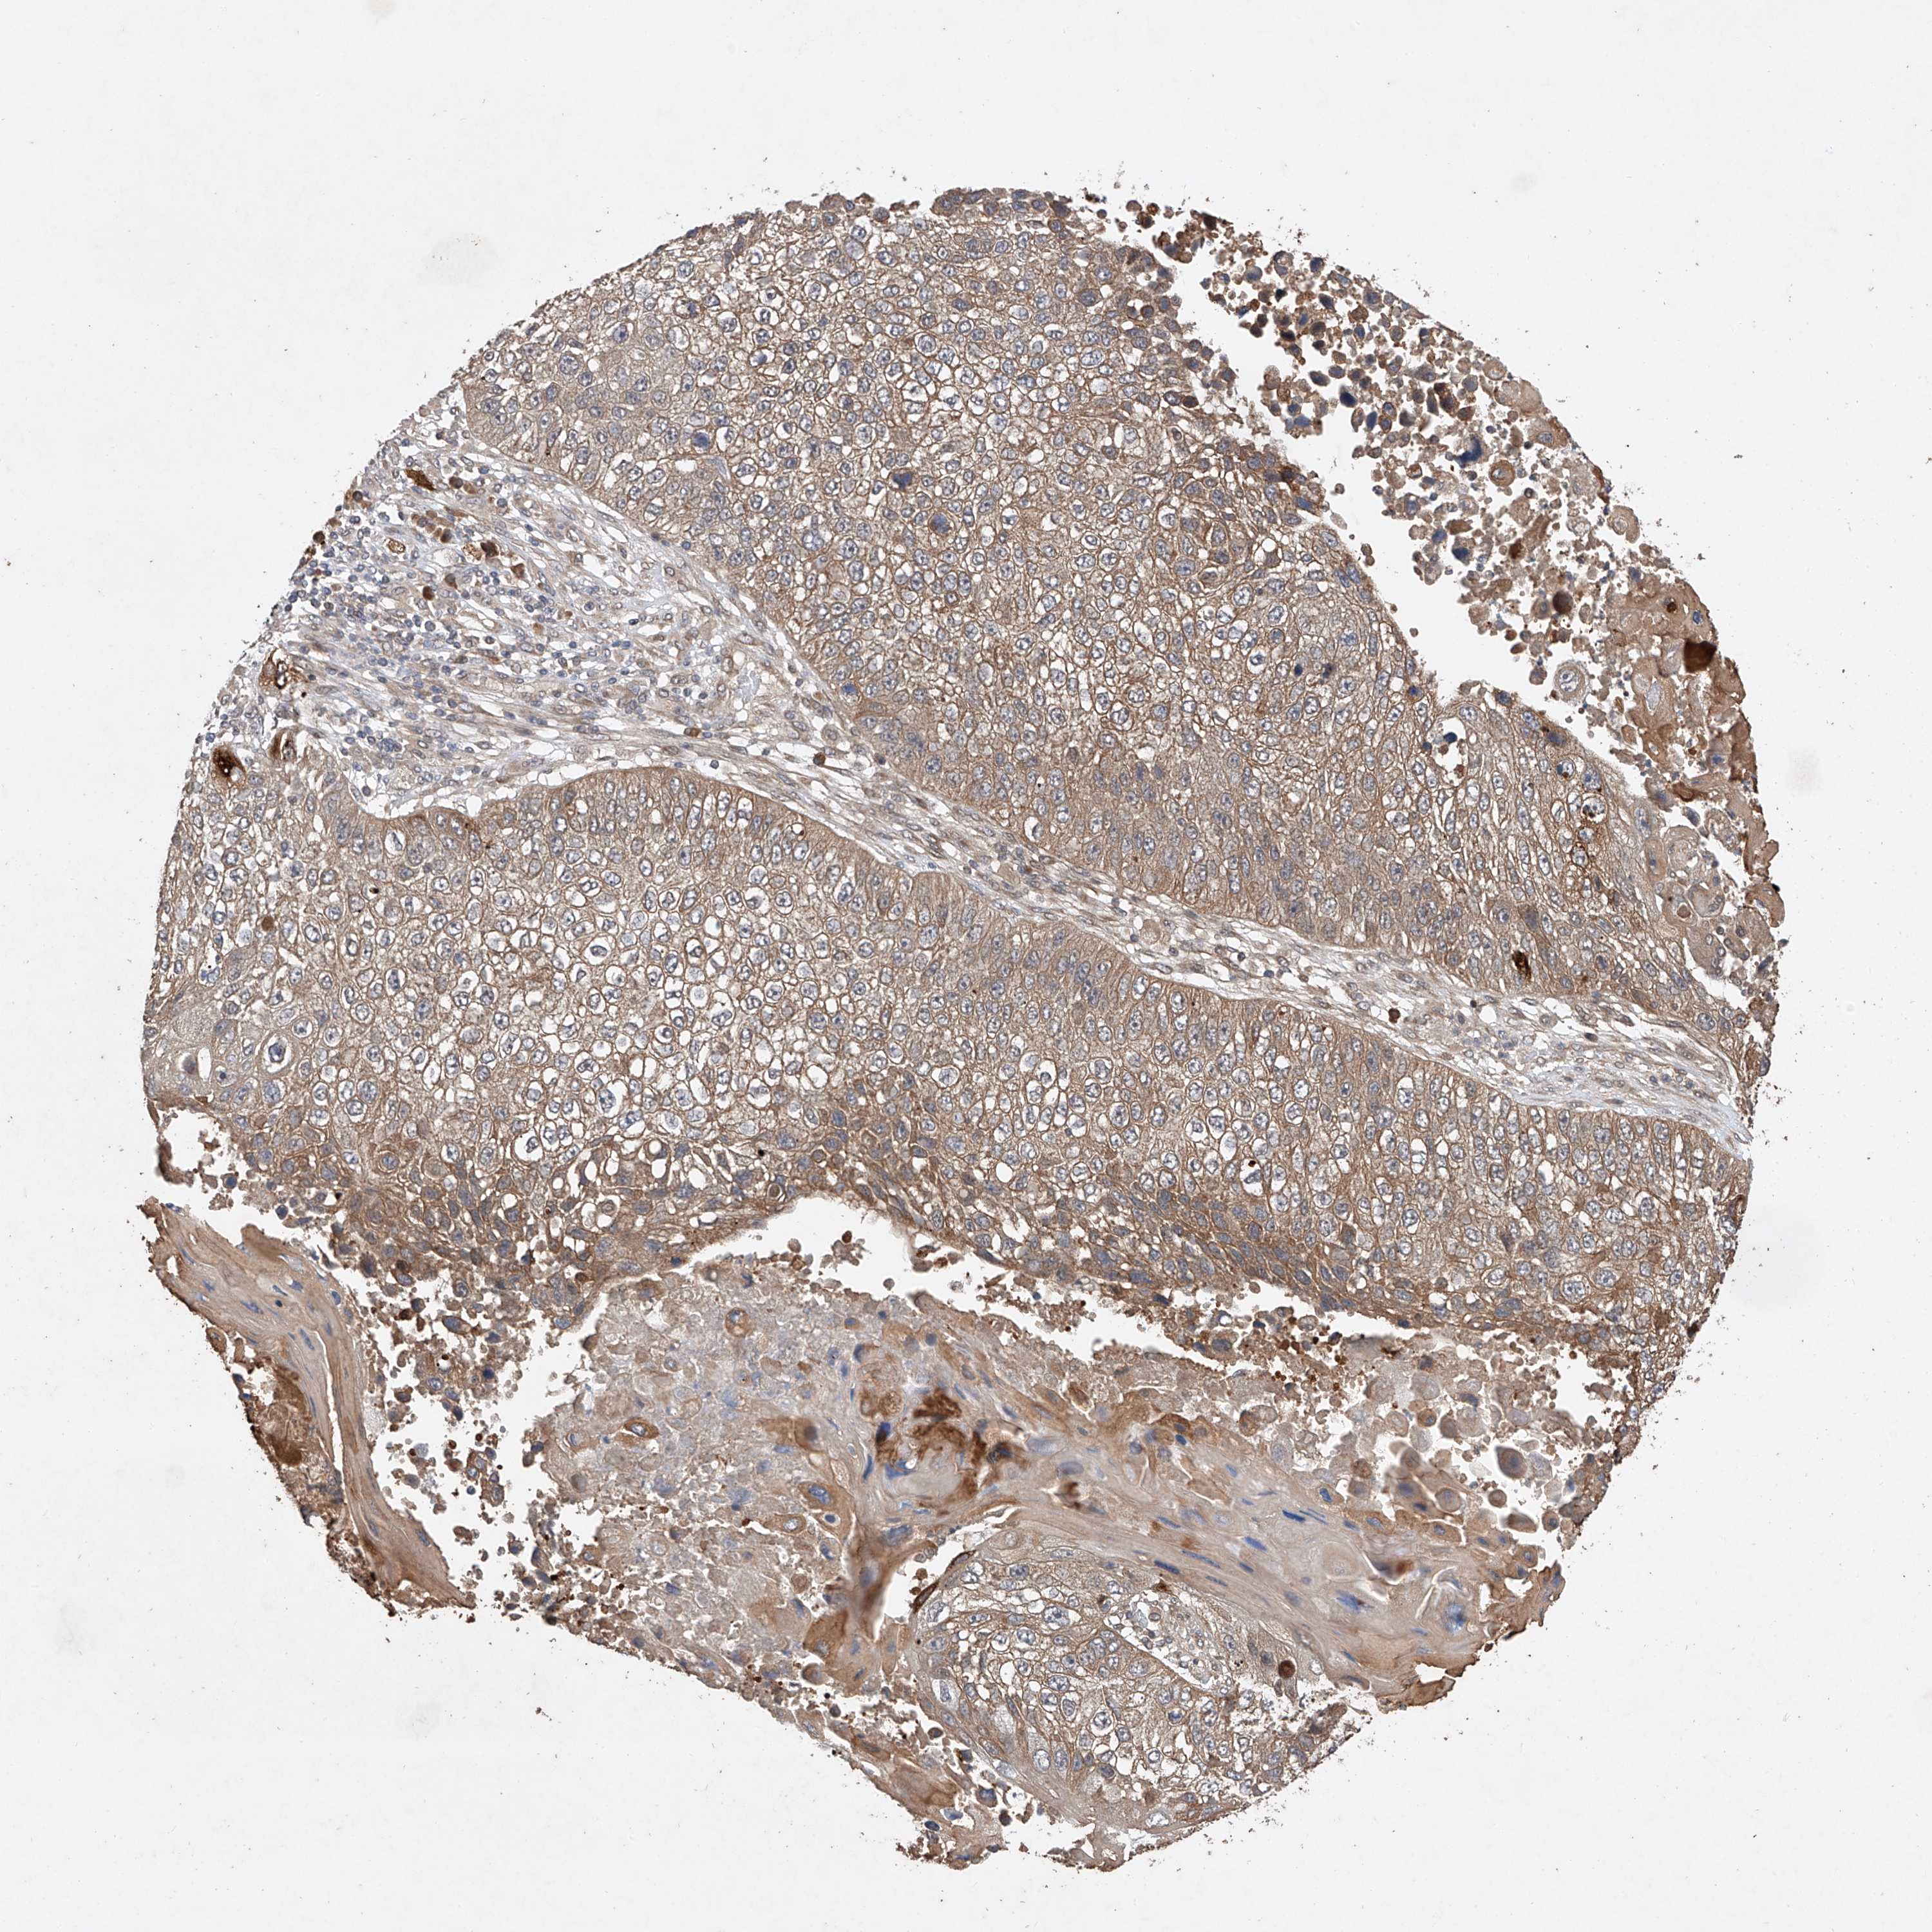

CANCER LUNG CANCER Show tissue menu

LUAD TCGA LUAD VALIDATION LUSC TCGA LUSC VALIDATION PROTEIN LUAD CPTAC PROTEIN LUSC CPTAC PROTEIN EXPRESSION

ANTIBODIES

AND

VALIDATION